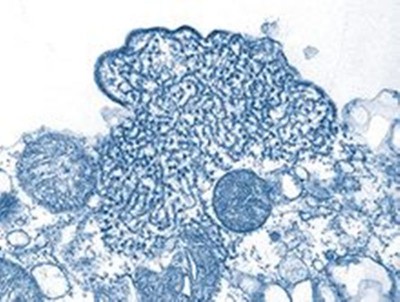

New York: A type of drug already used to treat obesity and Type 2 diabetes, when taken six months prior to the diagnosis of COVID-19, was associated with a decreased risk of hospitalization, respiratory complications and death in COVID-19 patients with Type 2 diabetes, according to researchers at Penn State College of Medicine.